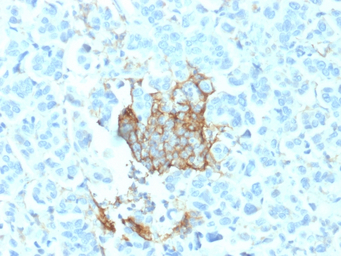

IHC-P analysis of human breast carcinoma tissue using GTX17979 p75 NGF Receptor / CD271 antibody [NGFR/1964].

IHC-P analysis of human melanoma tissue using GTX17979 p75 NGF Receptor / CD271 antibody [NGFR/1964].

IHC-P analysis of human adrenal gland tissue using GTX17979 p75 NGF Receptor / CD271 antibody [NGFR/1964].